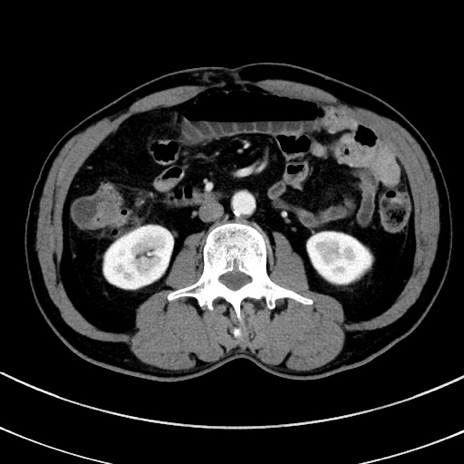

冠状断像

【症例】 60歳代男性

【主訴】 黒色吐物

【現病歴】 4日前から嘔気自覚、2日前の朝食後にも嘔気あり、自分で手で嘔吐反射起こし嘔吐したところ血が混ざっていたため受診。

【既往歴】 5年前汎発性腹膜炎を伴う急性虫垂炎で手術、高血圧、前立腺肥大症、高脂血症

【身体所見】 腹部正中に手術癩痕あり 腹部平坦・軟圧痛なし膨満感あり

【データ】WBC 8400、CRP 4.54